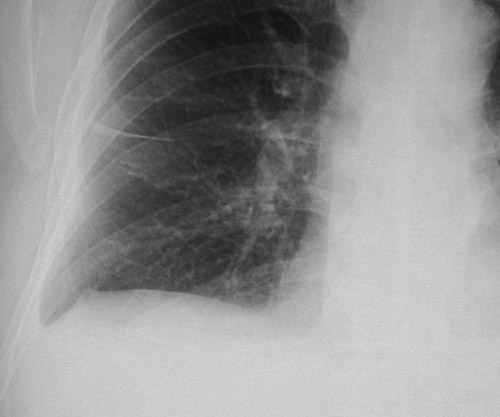

The magnified view of the chest radiograph in PA view on the right above demonstrates fluid in the major fissure in a patient with left heart failure. The magnified view of the fluid in the major fissure on the left is seen below.